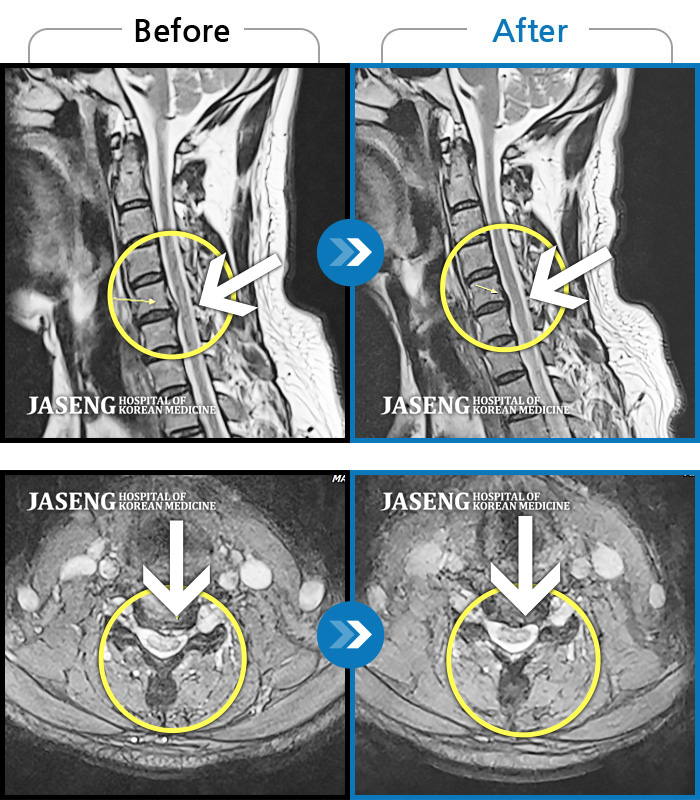

Before

After

환자에게 사전 동의를 받아 동일 조건에서 촬영되었습니다.

개인에 따라 치료 후 부작용이 발생할 수 있으니 의료진과 상담 후 치료를 진행하시기 바랍니다.

우측 엉치에서 발끝까지 저림

하요추부, 우측 둔부 통증 및 우측 하지 비증